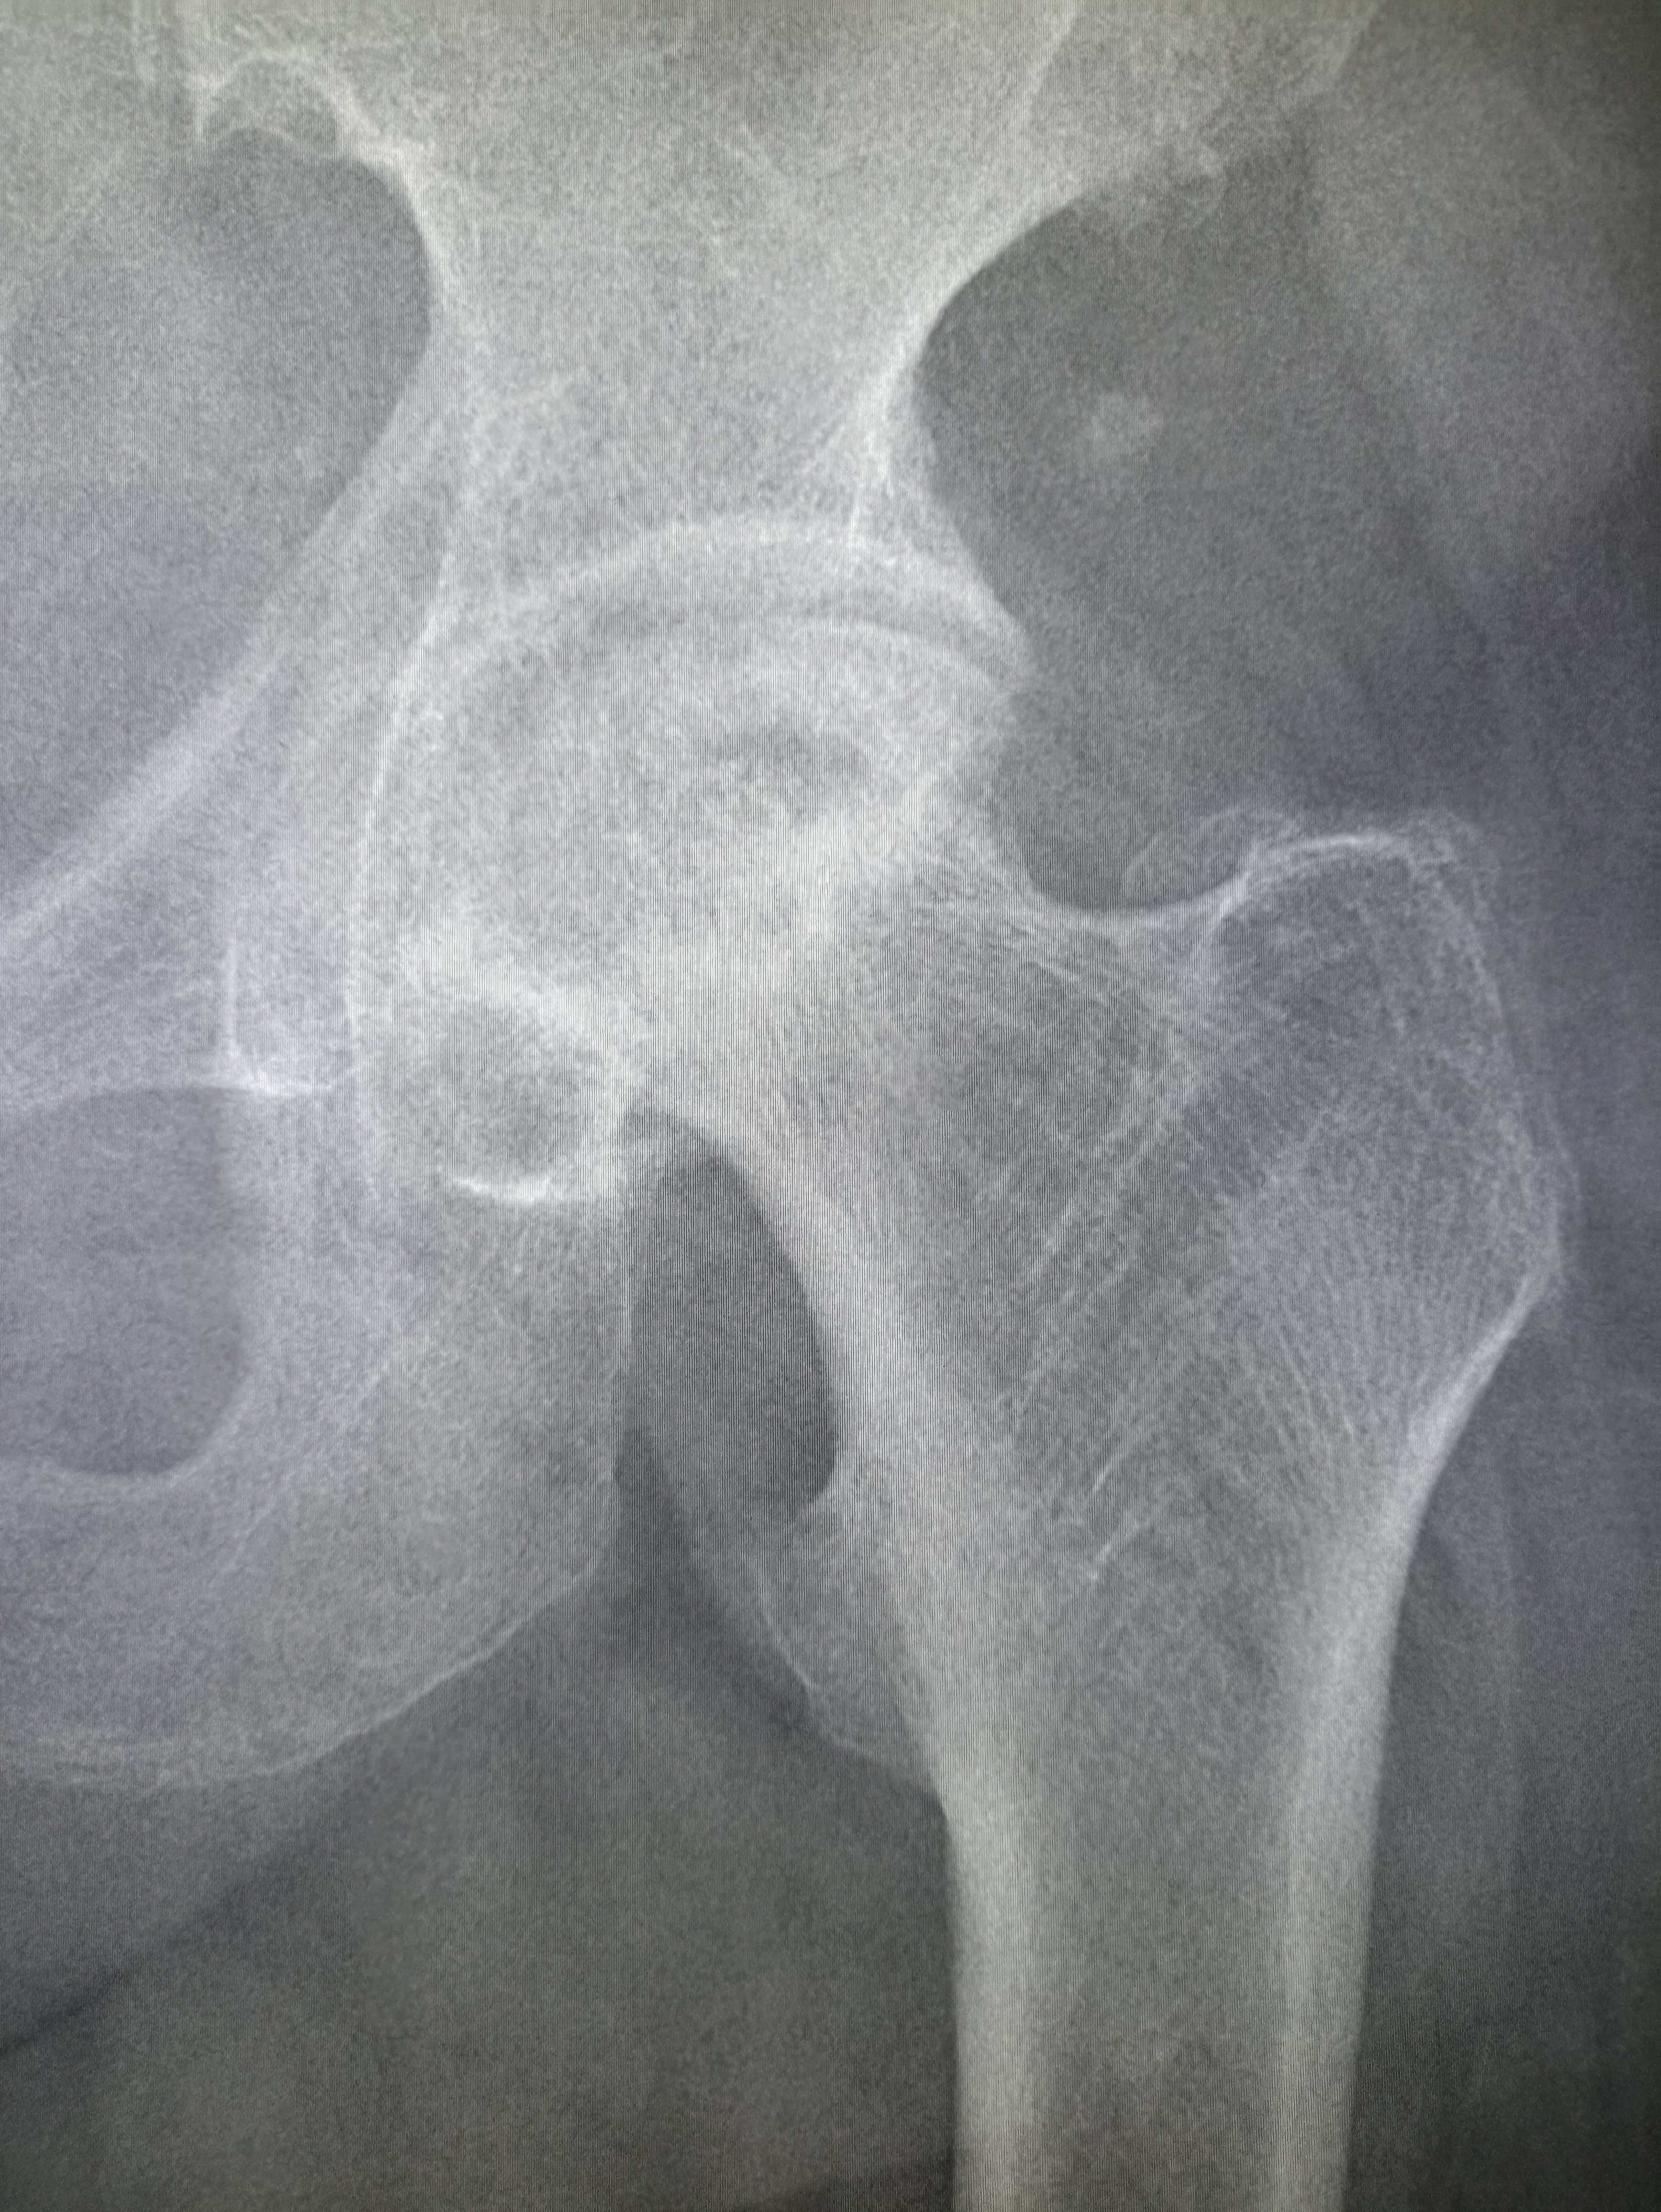

IMG20251016111451.jpg

Чо тут у нас ?

>>325600080

пизда твоей матушки

Коксоартроз